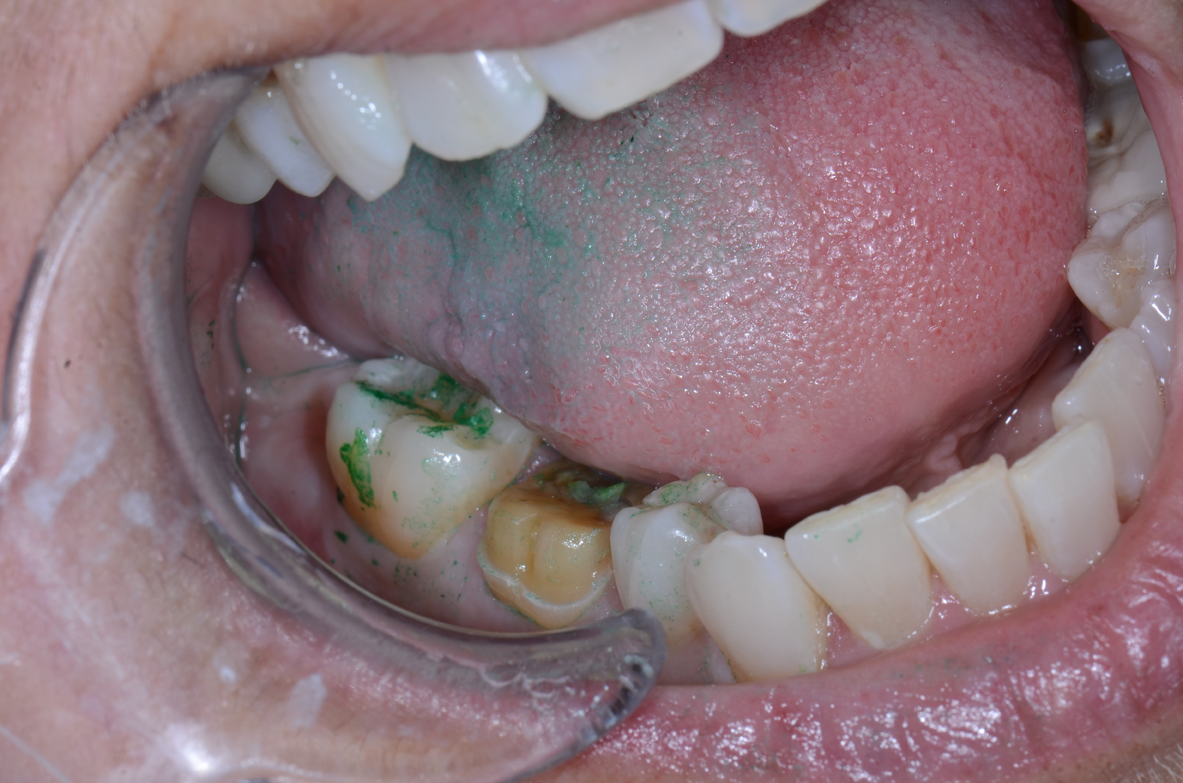

3. Apply pressure and use an explorer to determine whether or not the provisional is fully seated. Cure the material with an LED curing light for no more than one to two seconds from the lingual and repeat on the buccal. The material will now peel off easily and excess can be removed with an explorer or scaler (Figs. 12-15).

Fig. 13 Fig. 14 Fig. 15